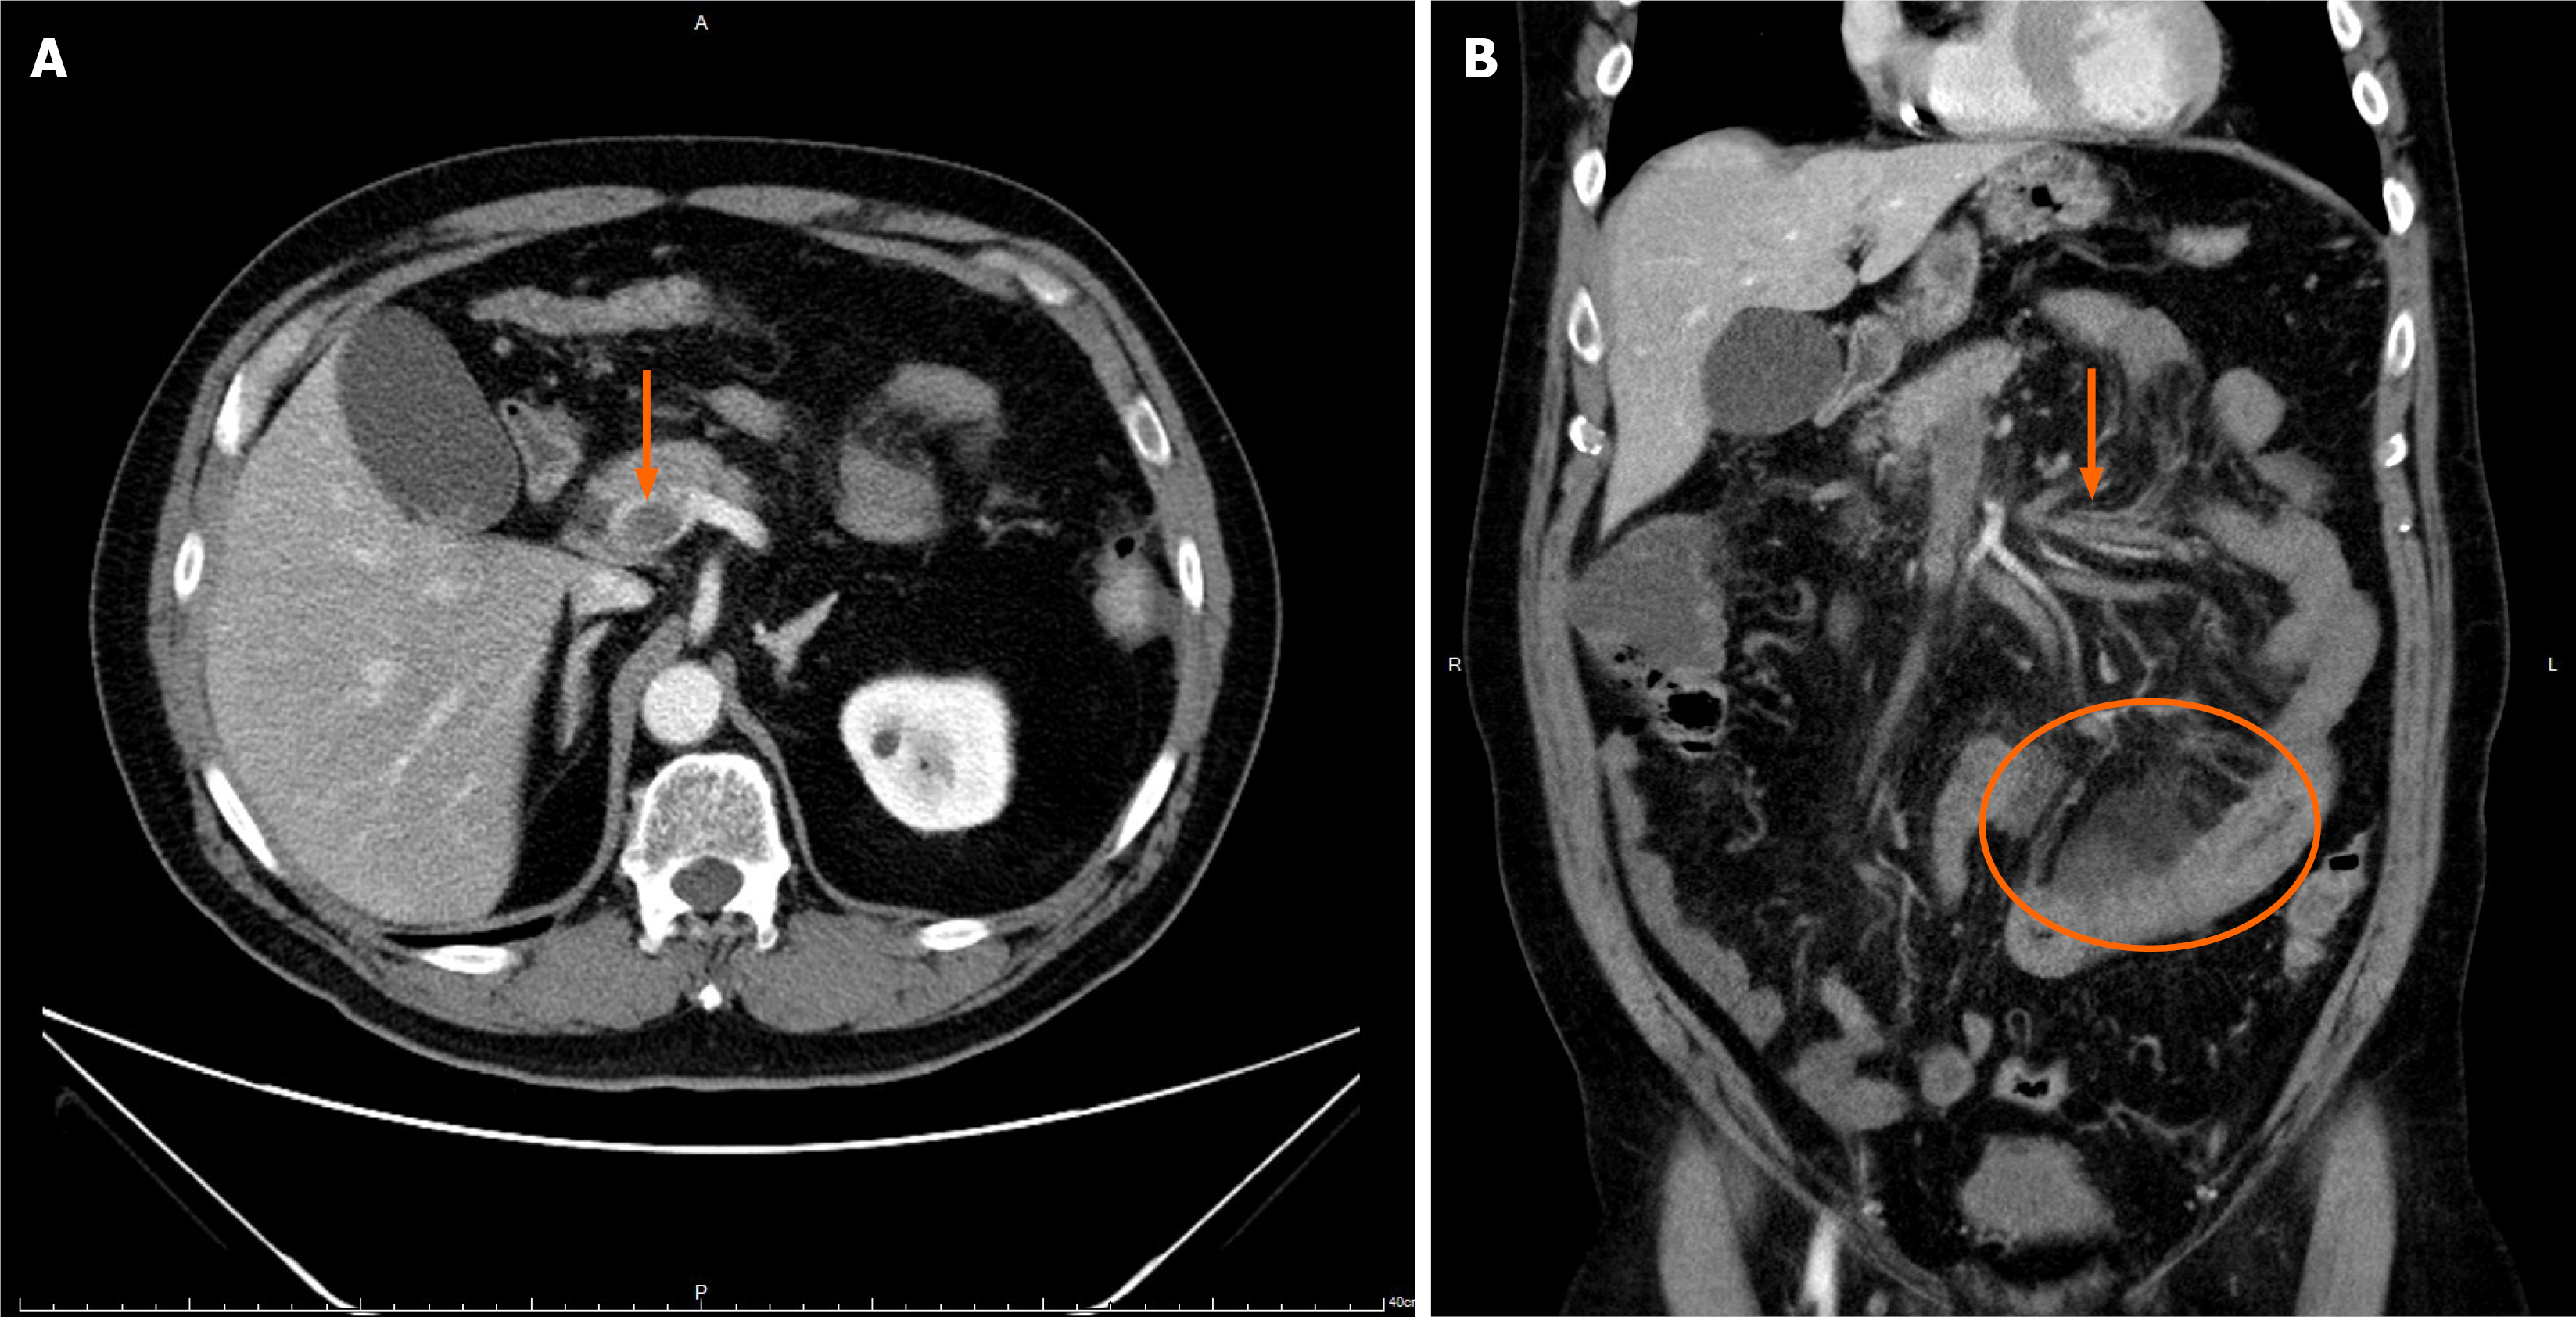

The patient experienced a self-limited episode of melena, resolving after urokinase tapering. His abdominal pain also subsided. The fibrinogen concentration decreased steadily throughout the course of treatment but remained above 100 mg/dL. A follow-up portal vein venography demonstrated portal vein patency with residual filling defects in the superior mesenteric vein branches, indicating partial thrombus resolution (Figure 2). After completing 14 days of CDT, the patient tolerated a soft diet and resumed normal bowel function. He was discharged on a therapeutic regimen of clopidogrel and apixaban.